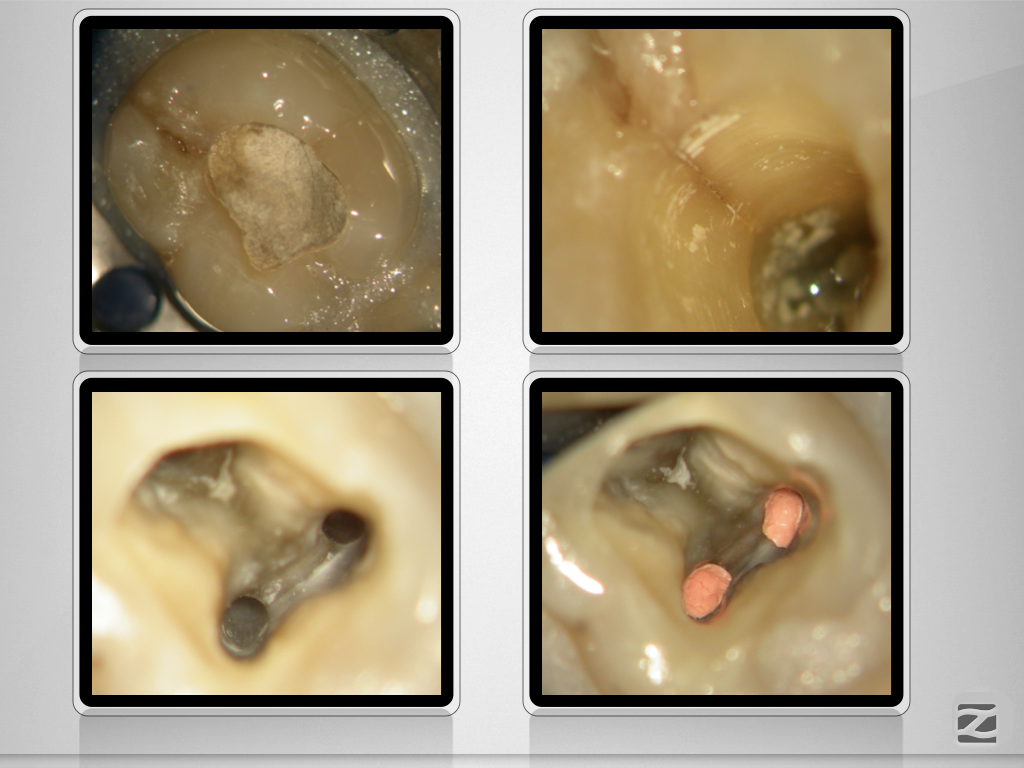

46D.010 Veröffentlicht 27. November 2019 am 1024 × 768 in Sensibilitätsstörung nach Initialbehandlung